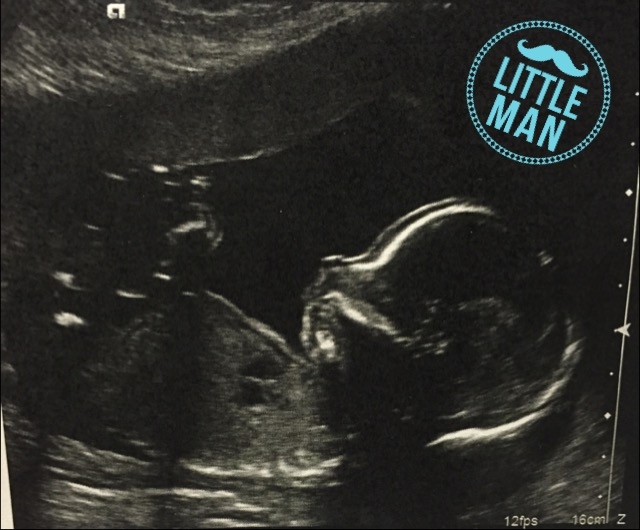

Baby boy at 19w1d! He was not being too cooperative in showing the tech everything she needed to see so it took a while and a lot of moving and jiggling. He had no problem mooning us and showing us his penis though!

It's a boy!!! I had a fair amount of belly pokes to get these photos, so worth it.